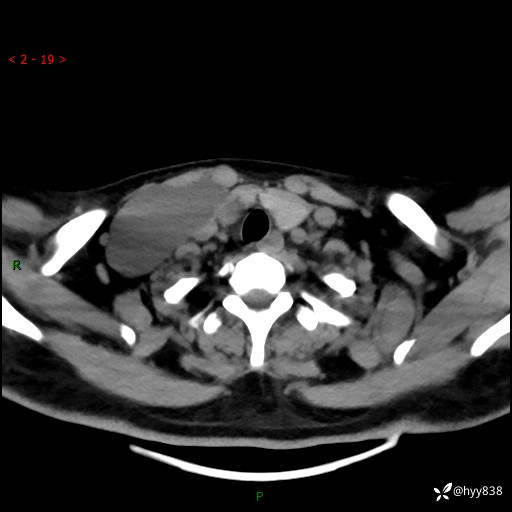

辅助检查:CT

颈部CT平扫

增强动脉期+静脉期